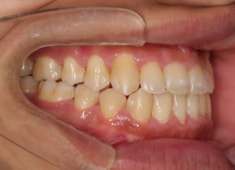

治療後(2年1ヶ月後)

大臼歯は整直されております。

歯根のパラレリングは良好です。

左上2番の歯根も問題なさそうです。

下顎8番は保定期間に入り、しばらくして咬合が安定してから抜歯する予定です。

特に左側の咬合時の顎関節の位置に改善が認められます。